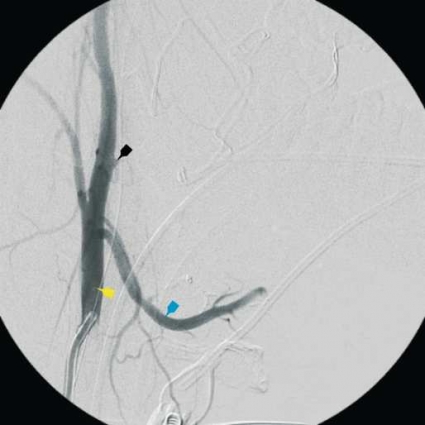

Han överförs direkt till intensivvårdsavdelningen, och inlagda kompressionstorkar fastsatta på peanger avlägsnas försiktigt. I det läget föreligger en mindre, sivande blödning basalt i vänster tonsillbädd. Det blödande området diatermeras. Eftersom det kliniska förloppet talar för en större kärlskada utförs direkt en karotisangiografi med planerad selektiv embolisering av blödningskällan. I samband med kateteriseringen av vänster arteria carotis externa börjar patienten plötsligt att blöda profust från vänster tonsillbädd. Kärlskadan lokaliseras angiografiskt till avgången för arteria facialis från arteria carotis externa (Figur 1–3). Ett första försök att stoppa blödningen selektivt i arteria facialis med intraarteriellt vävnadsklister misslyckas. Genom kraftig intern och extern kompression mot halsen kan blödningen hållas någorlunda under kontroll. I detta dramatiska läge beslutas att ockludera arteria carotis externa. Kärlet emboliseras med användande av platinacoils (Figur 4). Blödningen avstannar då omedelbart.